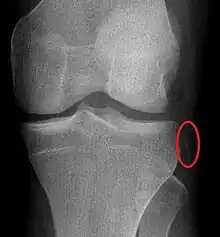

Segond fracture

Segond fracture of left knee

The Segond fracture is a type of avulsion fracture (soft tissue structures pulling off fragments of their bony attachment) from the lateral tibial plateau of the knee, immediately below the articular surface of the tibia (see photo).

Segond and reverse Segond fractures are characterized by a small avulsion,[5] or "chip", fragment of characteristic size that is best seen on plain radiography in the anterior-posterior plane. The avulsed fragment of bone may be very difficult to see on the plain x-ray exam, and may be better seen on computed tomography. MRI may be useful for visualization of the associated bone marrow edema of the underlying tibial plateau on fat-saturated T2W and STIR images, as well as the associated findings of ligamentous and/or meniscal injury.